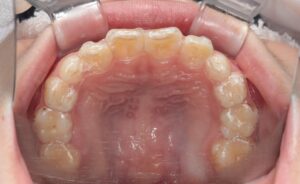

After |

治療途中の小児矯正の症例です。あごの成長を利用しながら、拡大装置で歯が並ぶスペースを広げ、

マウスピース矯正で歯の位置を少しずつ整えています。

After